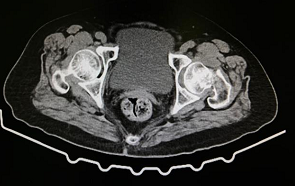

70岁的孙奶奶也成为了新政策的受益者。孙奶奶行走时不慎摔倒导致左髋部剧烈疼痛,无法站立和行走,家属急忙送到医院检查后发现是左侧股骨颈骨折。

包括股骨颈骨折在内的髋部骨折常被称为“人生最后一次骨折”,因为创伤对人体是一次打击,而很多老年人的基础情况较差,往往合并有慢性的心、肺疾病,如果保守治疗往往需要卧床休息。但长期卧床会引起肺部感染、褥疮等等并发症,严重时会危及老年人的生命。所以多等待一分钟,孙奶奶就多一分危险。对孙奶奶的身体进行详细检查后,第二天贾主任就给孙奶奶安排了人工全髋关节置换手术,手术十分顺利,孙奶奶术后第二天就可以在助行器辅助下站了起来。并在骨科进行了一周多的康复训练后顺利出院。